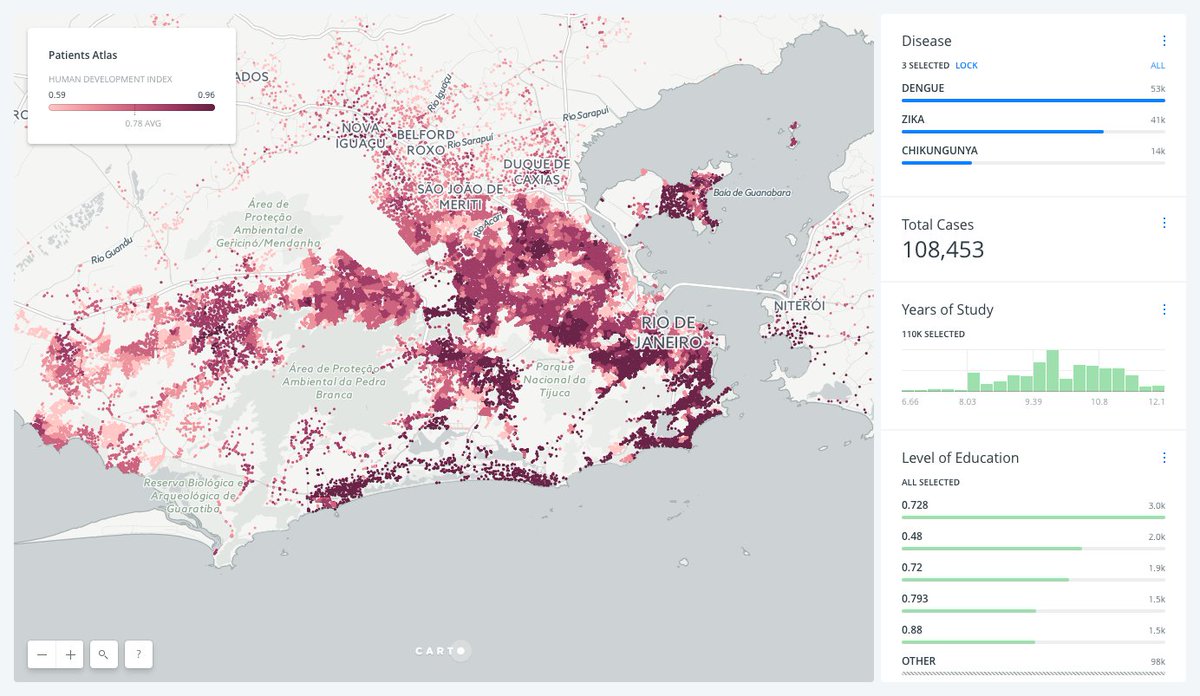

Understand and Predict Zika in Brazil with Spatial Analysis — CARTO Blog http://buff.ly/2i0wXdR pic.twitter.com/9wZfNwChDL